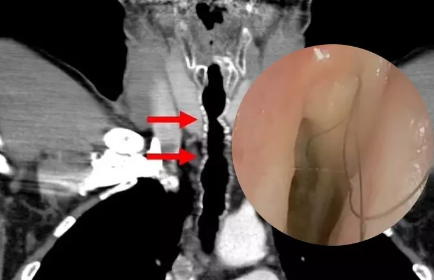

Həkimlər bildiriblər ki, adı açıqlanmayan 52 yaşlı şəxs səsin boğulma, nəfəs darlığı və xroniki öskürək şikayətləri ilə xəstəxanaya müraciət edib. Saçların bakteriya ilə örtüldüyü müəyyən edildikdən sonra ona antibiotiklər verilib. Ancaq təəssüf ki, saçlar növbəti 14 il ərzində hər il saat mexanizmi kimi uzanmağa davam edib. 52 yaşlı kişiyə endotrakeal tüklərin və ya boğazda tüklərin böyüməsi adlı olduqca nadir bir xəstəlik diaqnozu qoyuldu. Dəqiq bir şey deyə bilməsələr də, həkimlər saç artımının çox güman ki, siqaret vərdişlərindən qaynaqlandığını bildiriblər.